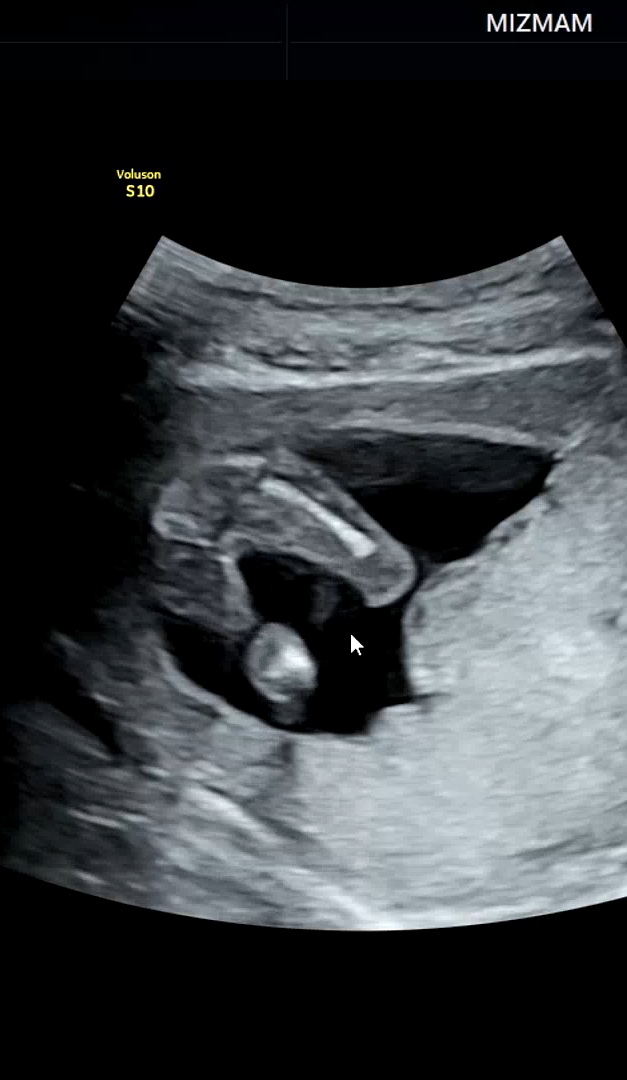

16주0일 성별반전 없겠죠??

12주때도 매끈했고 16주0일인 어제도 의사선생님께서 본인눈엔 ( 🌶가) 안보인다며 말씀 하셨는데 이러다 20주때 뭔가 뿅 생겨있을 가능성은...!! 얼마나될까요🤣